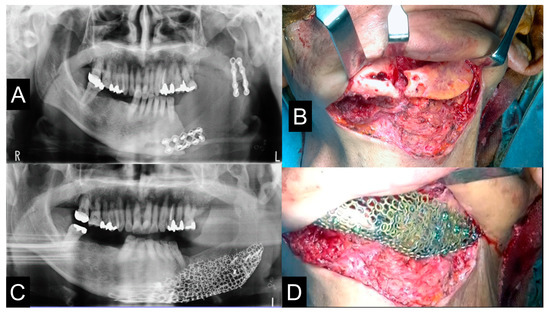

2.8. Clinical Procedures